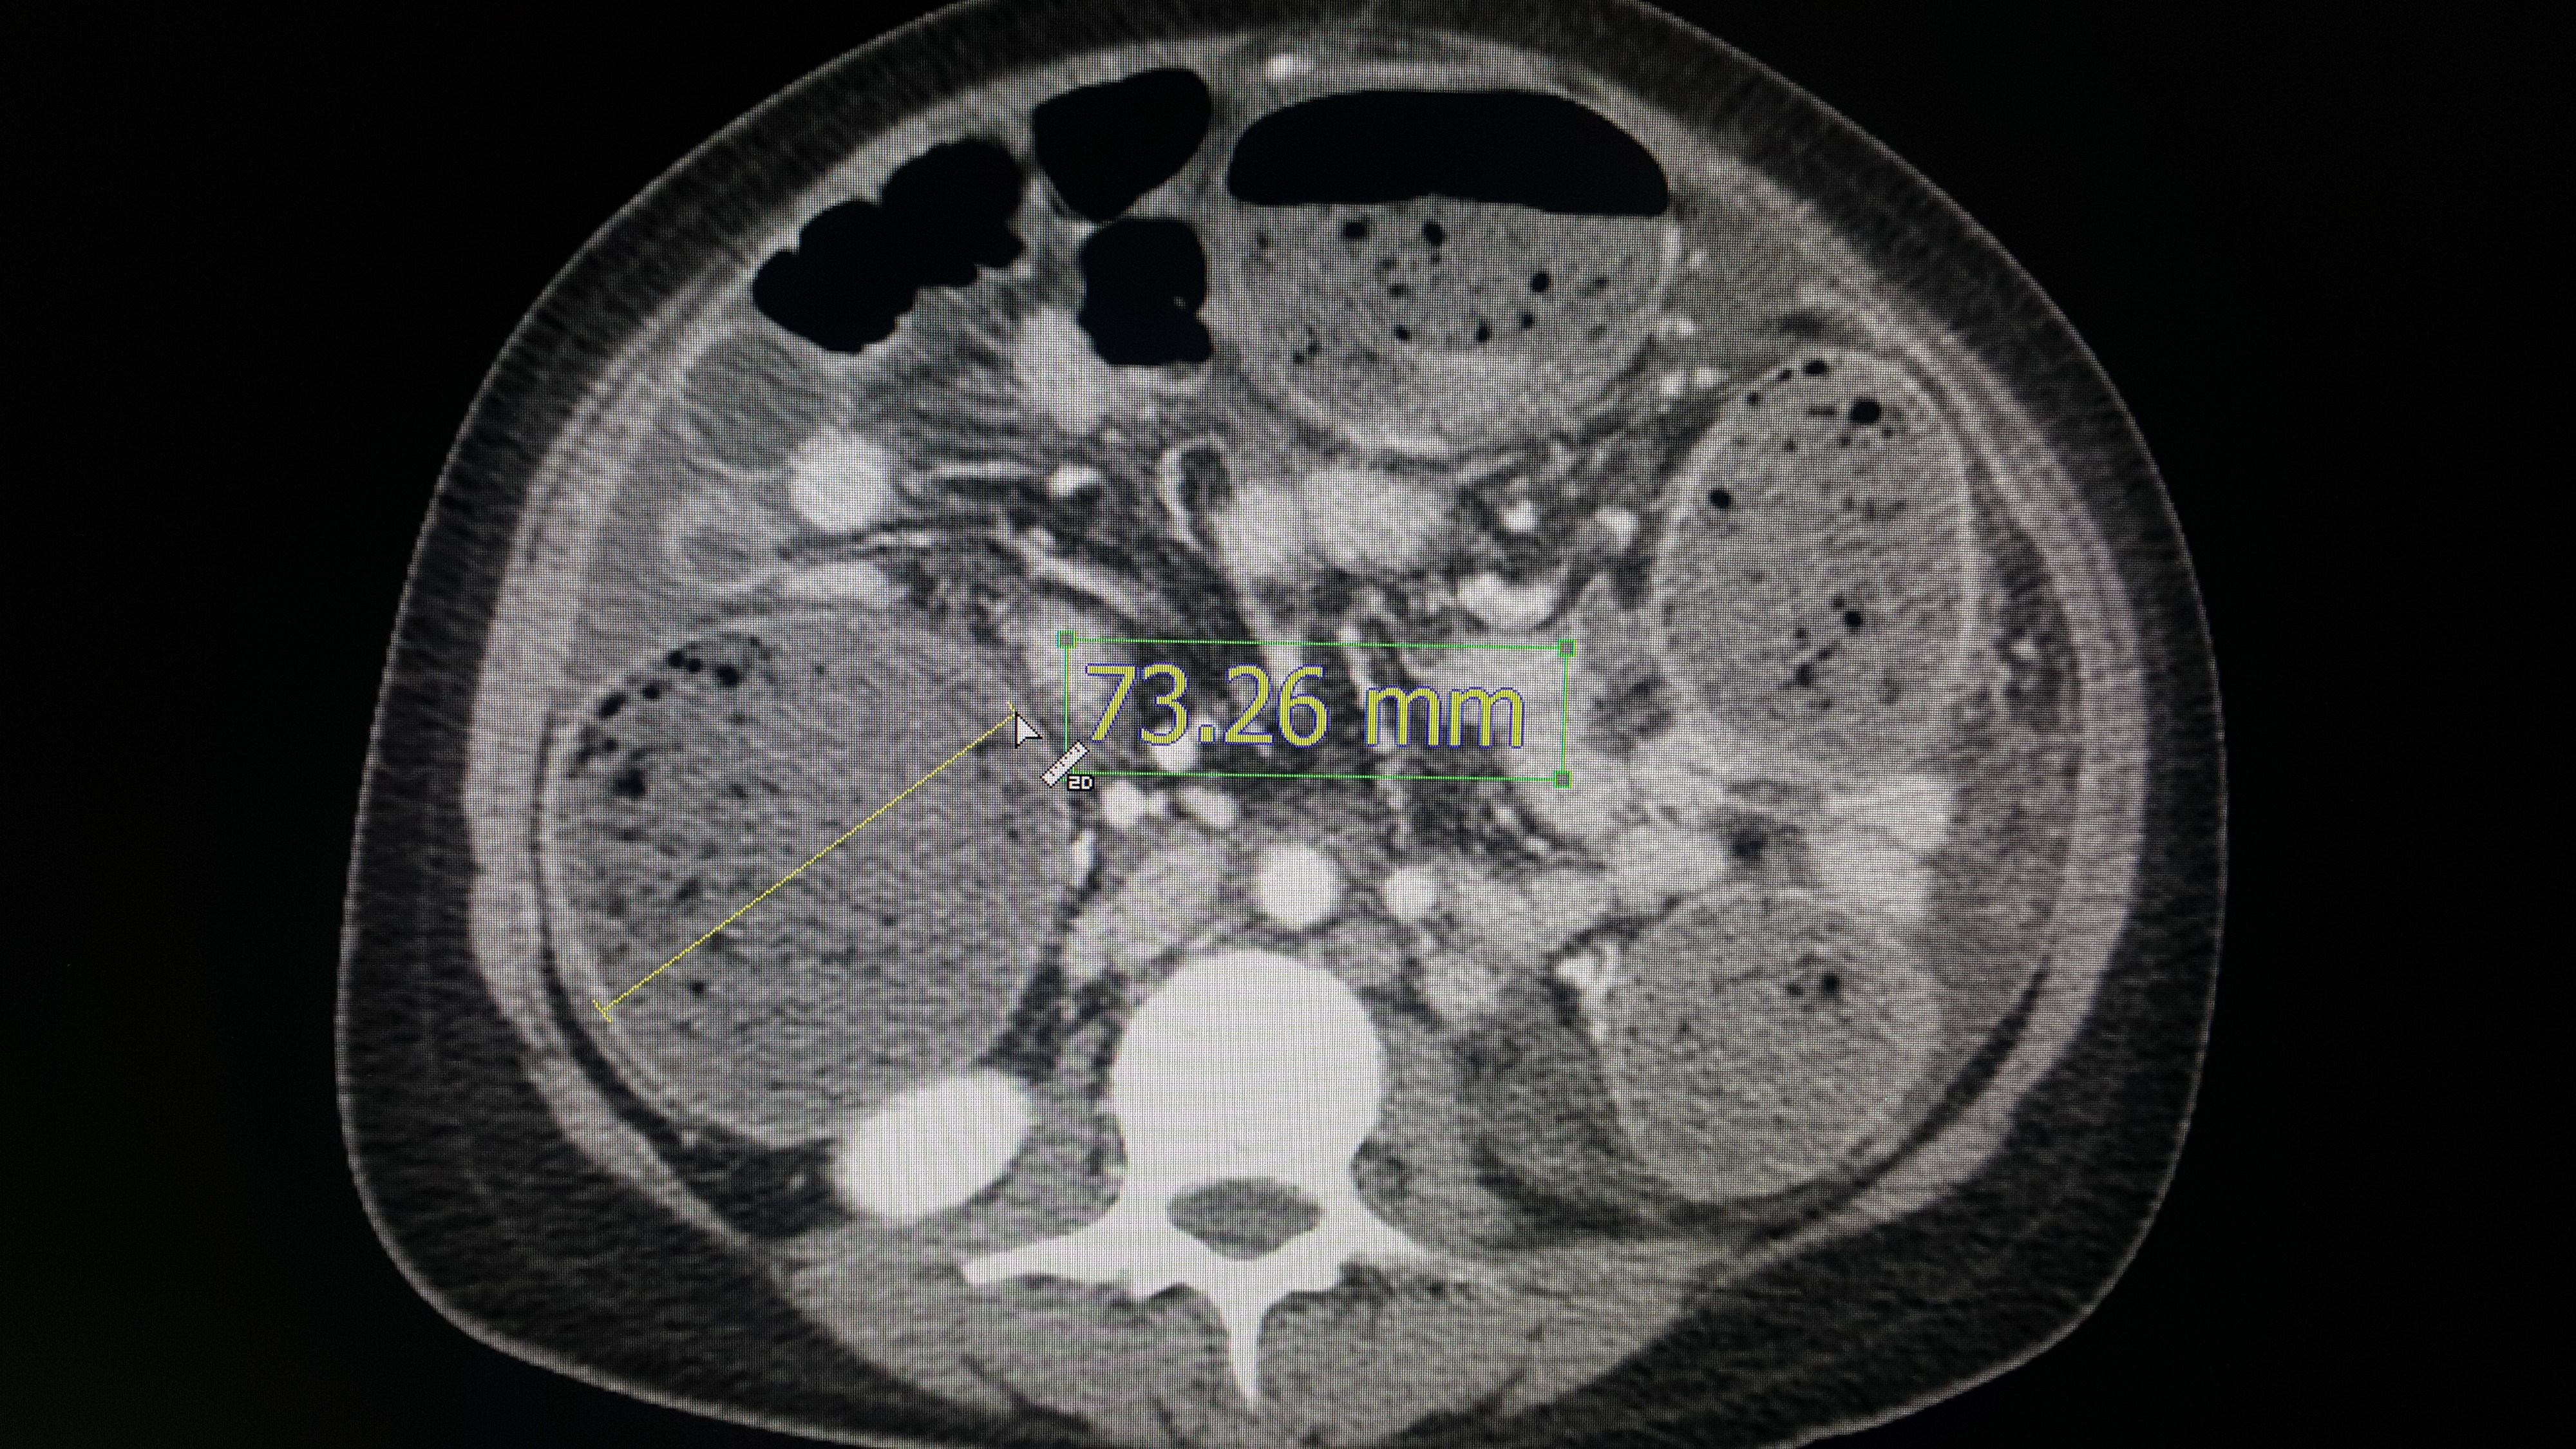

우후~~~~!!! 화살표로 크기를 측정한 부위는 대장이다. 대장 안에는 대변이 들어있는 것은 일반적으로 알고 있는 의학 상식일 것이다. 그런데 대장이 막혀서 늘어나있다. 그리고 그 크기가 무려 7cm 을 넘는다. 여러분은 직경 7cm 를 넘는 대변을 본 적이 있는가 ?? 그랬다면 아마 항문이 찢어져서 피가 났을 것이다. 하지만 이 환자는 막힌 대장으로 인해 대장이 저 정도로 늘어나있다. 얼른 막힌 대장을 뚫던지 임시로 대변이 나올 길을 만들어주지 않는다면 대장이 터져서 배 안이 대변으로 가득차는 위험한 상황이 생길 수 있다. 그래서 다른 병원에서도 급히 colostomy 라 불리는 대장을 배 밖으로 임시로 꺼내는 수술을 했을 것이다.